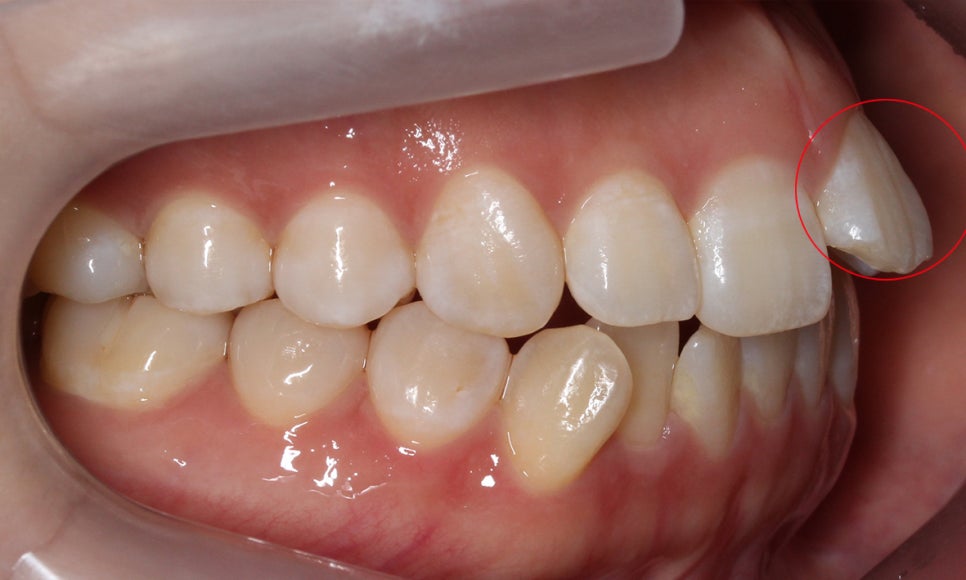

구치부에서 전치부로 이어지는 좌우의

교합평면을 확인해보면 양쪽 교합평면 모두

전치부의 앞니돌출 증상으로 인해 스마일라인이

가지런하지 못한 것으로 보이는데요,

이러한 증상들을 급속교정 으로 해결하기 위해

2D교정장치를 사용하여 설측에 브라켓을

부착하는 교정 계획을 수립하였습니다.